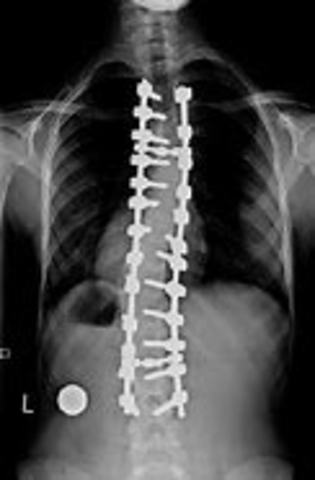

• X-ray Makes it to Surgery

X-ray Makes it to Surgery

First time the X-ray was used during surgery.